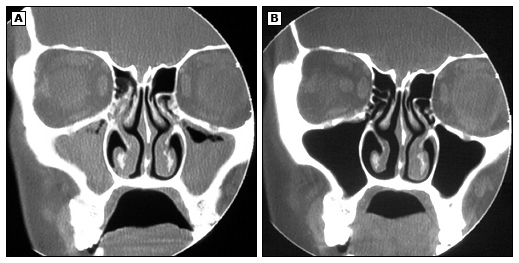

不伴息肉的鼻窦炎CT

这种类型的慢性鼻窦炎是最常见的,占60%-65%。

其临床表现是症状持续并周期性的加重,具有面部的疼痛、压迫感,鼻腔分泌物比较多。